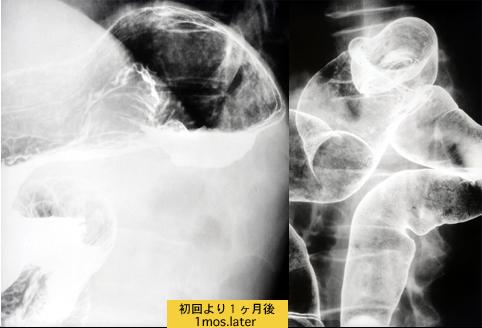

疾病(病理主体)的分类肿瘤样病变/来自相邻脏器的浸润

部位(按器官分)大肠/降结肠

检查方法X线

肿瘤最大直径35~40